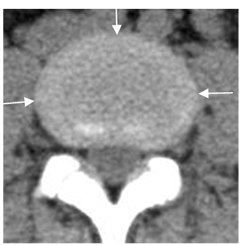

En TAC el anillo fibroso puede ser un poco mas denso, que el núcleo pulposo. (5). (Fig 16).

Fig 16. Disco normal en TAC.

TAC axial: Núcleo pulposo normal, con anillo periférico un poco mas denso. (Flechas).